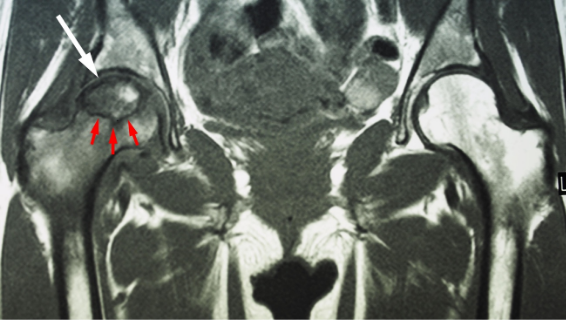

- Ressonância magnética (padrão-ouro para diagnóstico precoce)

A ressonância permite identificar lesões antes do colapso estrutural — momento ideal para intervenção preservadora.